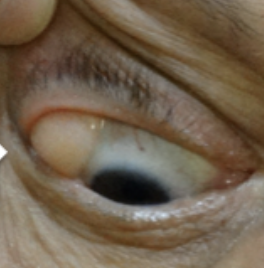

Sunken Eyeballs/Enopthalmos

Abnormal findings for 1. Position and alignment of the eyeball in the eye socket

“eyebags”, sunk in your face. Family history, dehydration and lack of sleep.

usual to severely dehydrated px

Seen with severe dehydration or chronic wasting illness